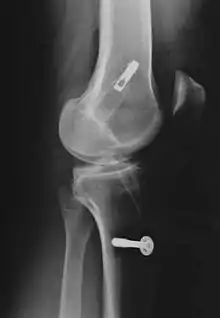

| Anterior cruciate ligament reconstruction | |

![]() Arthroscopic anterior cruciate ligament (ACL) reconstruction (right knee). The tendon of the semitendinosus muscle was prelevated, folded and used as an autograft (1). It appears through the remnant of the injured original ACL (3). The autograft then courses upwardly and backwardly in front of the posterior cruciate ligament (2). | |